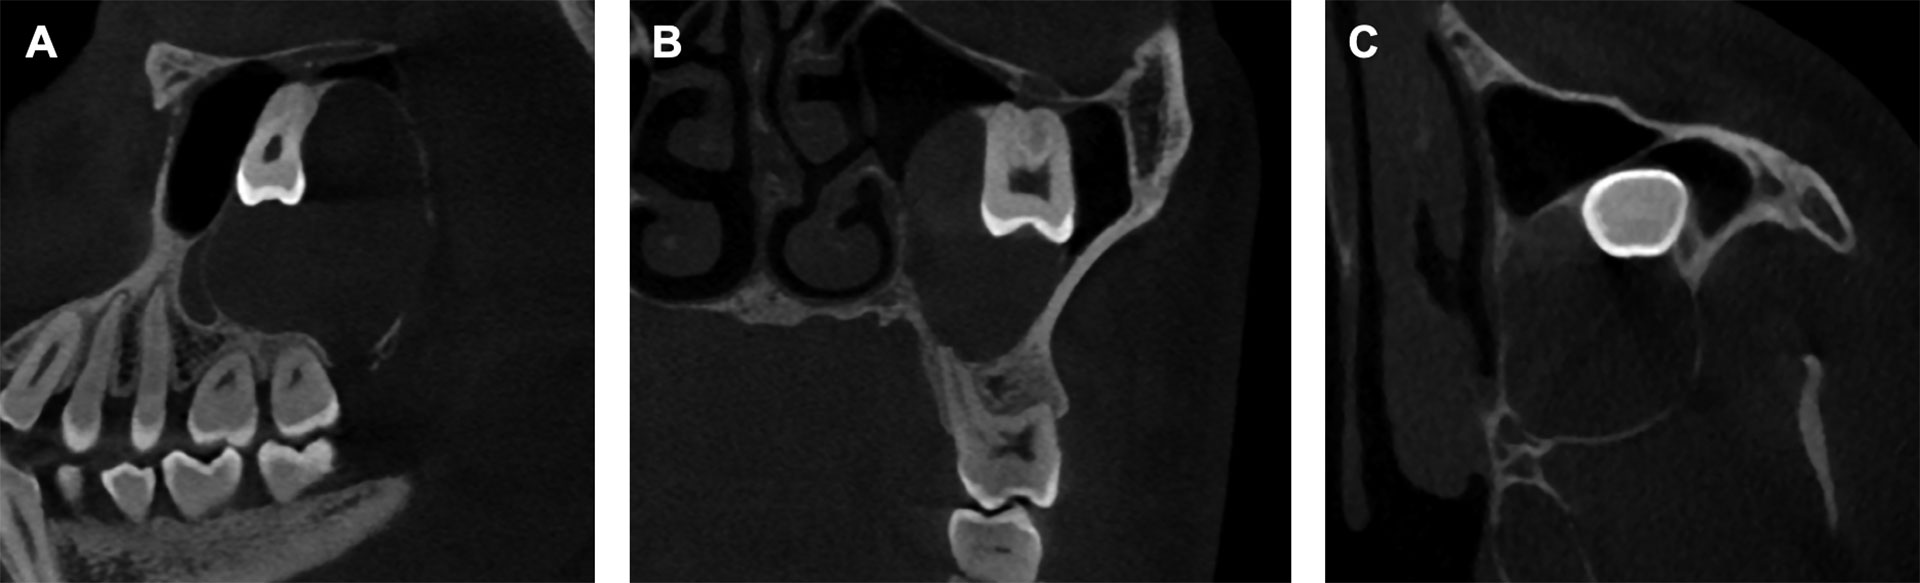

Panoramarøntgen og CBCT viste retinerte visdomstenner 18, 28, 38 og 48 (figur 1). Det ble påvist en stor cystisk prosess som fylte ut deler av den venstre delen av kjevekammen i overkjeven, samt en betydelig del av venstre maxillarsinus. Prosessen hadde en tynn bengrense mot den ellers luftfylte øvre delen av bihulen. Det forelå fortynning og ekspansjon av både lateral og posterior sinusvegg. Tann 28 var displassert kranialt i retning orbitagulvet (figur 2). Marginalavgrensningen av prosessen var noe utvisket, og det forelå lett resorpsjon av apices på tann 26 og 27 (figur 1 B). Radiologisk tentativ diagnose var en cystisk prosess, mest forenlig med enten en keratocyste eller follikulærcyste i venstre del av maxilla og maxillarsinus.

Figur 2. Preoperativ CBCT av regio 23-28 hvor nevnte tenner, cysten og venstre maxillarsinus også omfattes. A: Sagittalt CBCT snitt viser tann 28 og cysteomfang mot noe luft cranialt i bihulen. B: Coronalt CBCT snitt viser cranialt displassert tann 28 med apikalområdet mot orbitagulvet. C: Axialt CBCT snitt viser krone tann 28 og ekspandert posterior bengrense for venstre maxillarsinus.